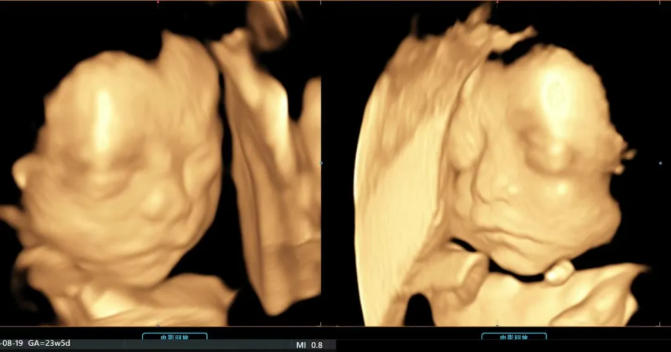

而四维彩超,就是孕期里最浪漫的“约会”

跨越肚皮的阻隔,清晰看见宝宝的模样

定格生命最初的美好,也为宝宝的健康保驾护航

艾玛妇产拥有超声影像进口GE设备,作为前沿器械,可以堪称为妇产领域超声的“战斗机”,其带来的强劲处理能力,成就了全新的渲染重建技术,全面颠覆传统视觉理念,带来前所未有的影像质量。同时能够提供更多的图像数据,实现在扫描同时即刻呈现胎儿标准生长曲线和相应测量数据,实时的结构信息及功能成像为临床精确诊断和评估提供坚实可靠的图像支持。

艾玛妇产的超声影像拥有独立的诊室,双彩高清显示屏,不仅能让来做检查的宝妈可以看到宝宝,陪同的家属同样可以一起近距离观察宝宝的一举一动噢~

六 四维影像留念

医生在做筛查时会抓取部分照片和视频片段赠送给宝爸宝妈以作留念。